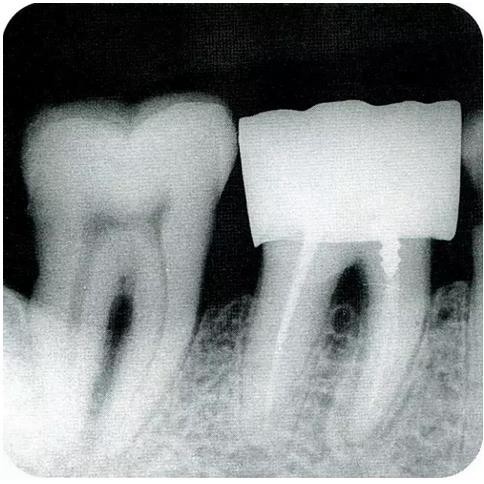

▼圖6-1 下頜第一后磨牙的頰舌間存在III度的根分叉病變,預(yù)在進行牙根分割后保留遠中根。

▼圖6-2 中下頜第一后磨牙雖然切除了一半,但是遠中根也有2根分根,所以不得已拔除(被拔除遠中根的近中面觀察)。